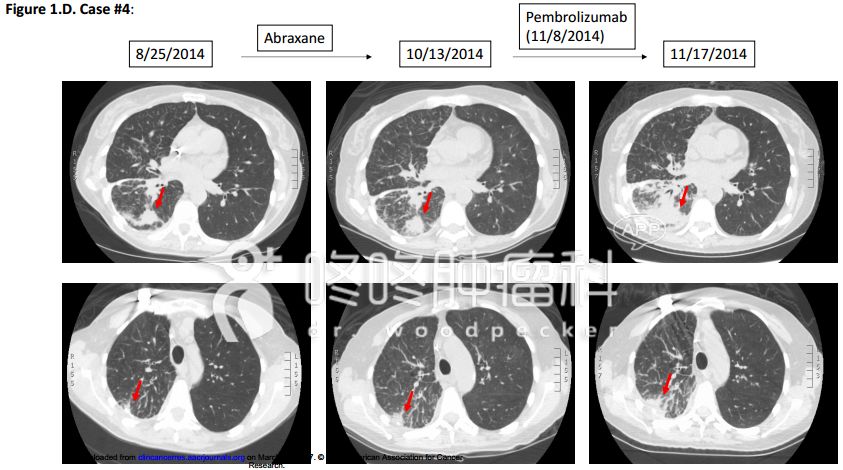

这是一个例子:患者50岁,肺腺癌,基因检测显示MDM2扩增,伴随KIF5B-RET融合,使用白紫化疗无效,之后改用PD-1抗体Keytruda,用药9天之后,患者的状态急剧恶化,严重的乏力,CT检查发现一个月之后患者的肿瘤增大了很多(原文的描述是:9天时间增大1.3倍)。影像数据如下: